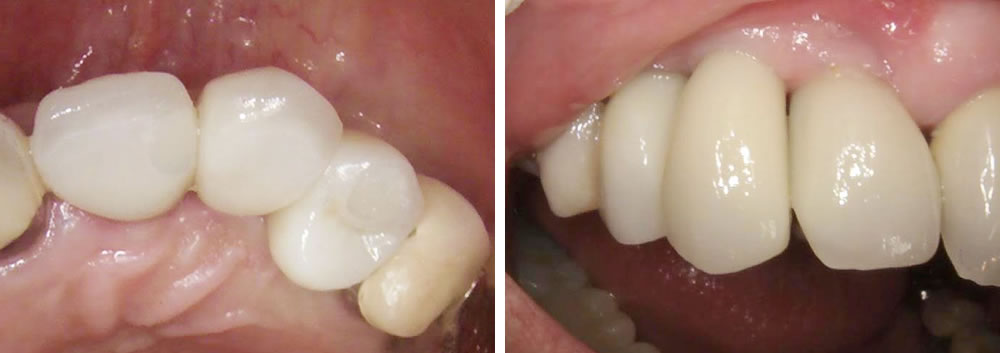

インプラント治療完了後の口腔内写真

抜いた時には唇側の骨が欠損してしまっていましたが、無事歯茎が下がる事を最小限に抑え上部の歯を作成する事ができました。